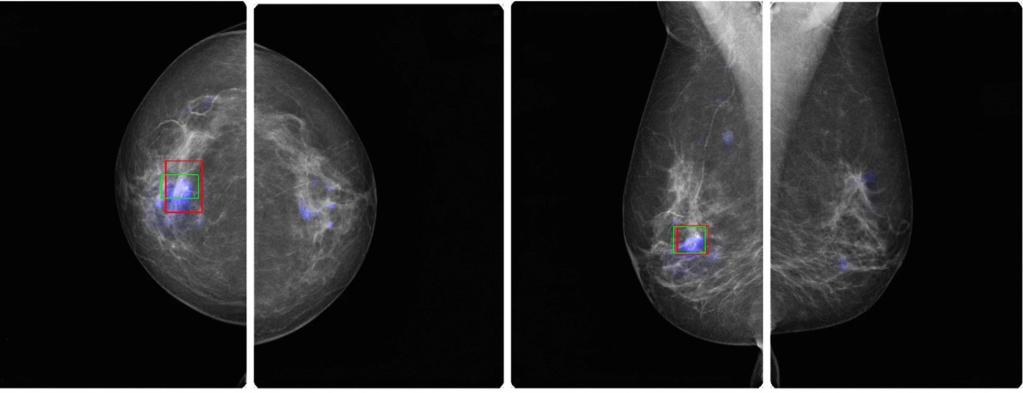

KI Software

Die von uns verwendete KI Software stammt von der Schweizer Firma b-rayZ AG. Sie wurde an tausenden von Mammographien mit gesicherten Befunden "angelernt" (Machine Learning). Die Software wird im Rahmen des Qualitätsprogramms QuaMaDi eingesetzt, kommt aber bei uns auch Patientinnen zugute, die nicht an QuaMaDi teilnehmen (können).